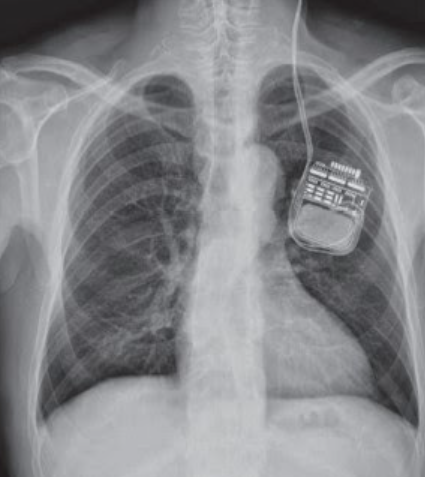

The procedure involves:

Removing the old battery from the chest area

Connecting a new battery to existing leads